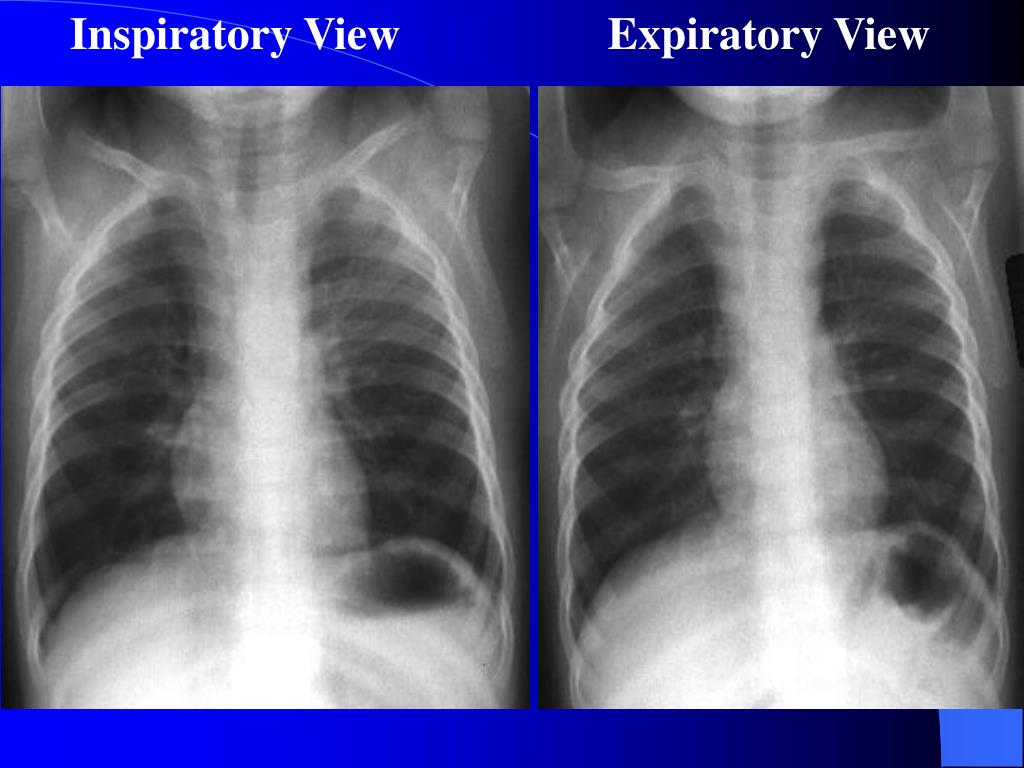

30. Inspiratory View Expiratory View

34. Investigations • Xrays • Lateral neck • Chest – inspiratory, expiratory, decubitus views • Expiratory views • Overinflation (partial obstruction with inspiratory flow) • Volume loss with mediastinal shift towards obstructed • side (partial obstruction with expiratory flow) • Atelectasis (complete obstruction)

35. Decubitus views Normal Smaller volumes and elevated diaphragm on side down Abnormal Hyperinflation or “normal” volumes in decub position If suspected … Need a bronchoscope to rule out or remove Foreign Body